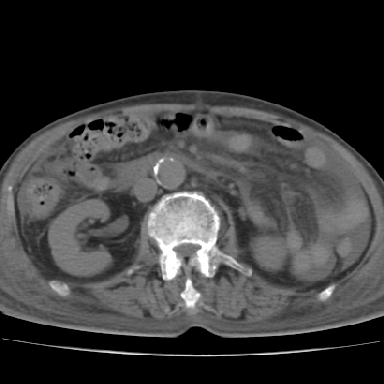

以下是引用qian在2006-12-4 19:11:00的发言:[br]胸腔和腹腔内均见有液性影,肝上极包膜下有一较大椭圆形低密度影,密度均匀,边缘清晰,结合病史考虑术后肝脓肿并胸腹腔积液。

以下是引用chry3在2006-12-4 21:05:00的发言:[br]应该往上扫几层,我考虑膈下脓肿。[br]大家考虑:胃部手术怎会造成肝内脓肿,隔下脓肿到是会造成的

以下是引用dyqct在2006-12-4 19:54:00的发言:[br]考虑:1、肝包膜下脓肿;[br] 2、少量腹水;[br] 3、右侧少量胸膜腔积液。